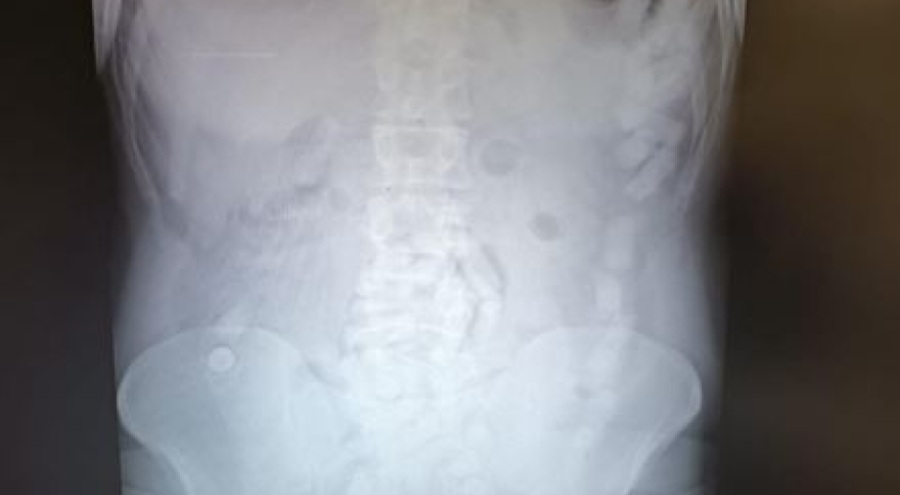

Şüphelinin bulunduğu yolcu otobüsü durduruldu. Gözaltına alınan R.K., muayene edilmek üzere Kayseri Şehir Hastanesi'ne getirildi. Röntgeni ve ultrason çekimi sonrası yapılan kontrollerde R.K.'nın mide bölümünde uyuşturucu madde kapsülleri yutmuş olduğu belirlendi. Şüphelinin midesinde yaklaşık 100 kapsül içinde 729 gram metamfetamin olduğu tespit edildi. Uyuşturucular sağlık ekiplerince yapılan tedavinin ardından çıkarıldı.